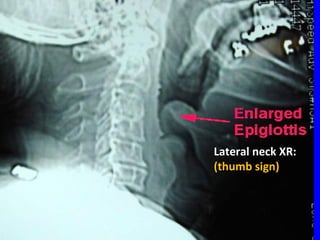

โ€ข Dx:Dx:

โ€“ โ€œโ€œcherry redโ€ epiglottischerry redโ€ epiglottis

โ€“ โ€˜โ€˜thumb signโ€™ on lateral neck XRthumb signโ€™ on lateral neck XR

Lateral neck XR:Lateral neck XR:

(thumb sign)(thumb sign)